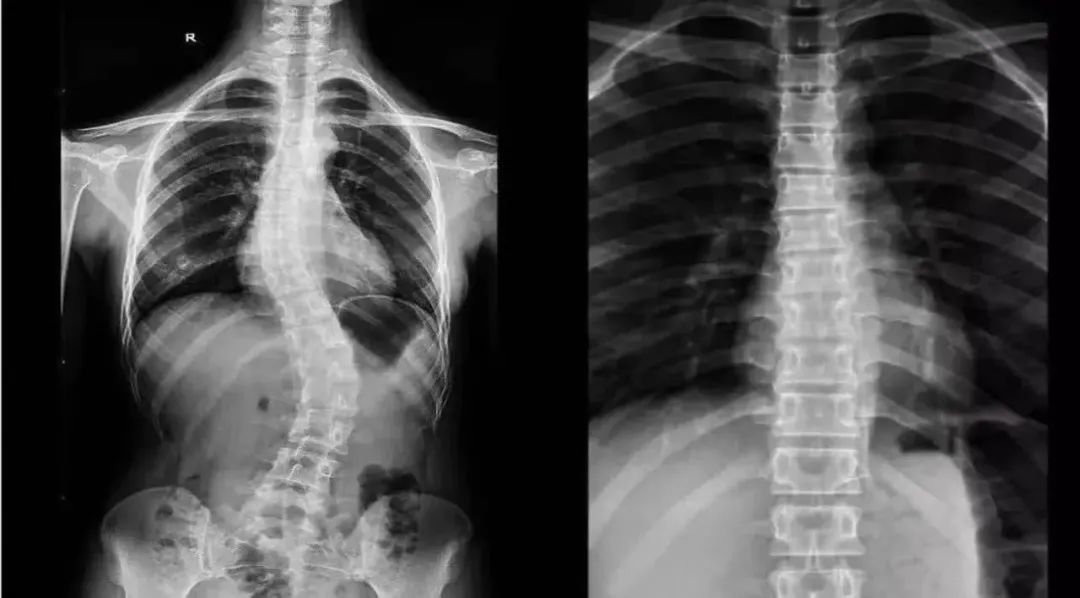

脊柱侧弯是指脊柱偏离身体中线向侧方弯曲,形成一个维度或多个维度方面的脊柱畸形,会导致一系列姿势体态、功能活动异常、疼痛等。临床上只有当侧弯角(Cobb角)>10°的时候,才能诊断为脊柱侧弯

3D体态扫描+专业医生触诊,精确测量Cobb角,根据侧弯类型(C型/S型)及程度制定个性化矫正计划。

▷ 青少年特发性脊柱侧弯(Cobb角10°-40°)